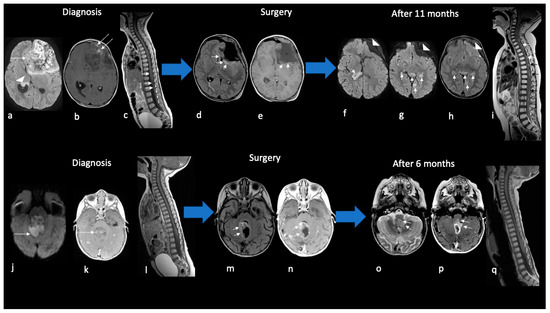

In four pediatric patients (40%), tumors showed leptomeningeal spreading at diagnosis, either in intracranial cerebrospinal fluid (CSF) or in intracranial and spinal CSF (Figure 4).

Figure 4.

Imaging findings of disease progression in children with ATRTs. Ax DWI (a,f,g,j); Ax T1w (e); Ax T1w+mdc (b,k,n,p); Sag T1+mdc (c,i,l,q); Ax FLAIR (d,h,m); Ax T2w (o). An about 2-year-old child with frontal ATRT (a–i). At diagnosis, axial DWI MR shows reduced diffusivity of ATRT at the primary site in the frontal lobe (arrow in (a)) and at metastases in the lateral ventricle (arrowhead in (a)); mild enhancement is present (arrows in (b)). Sagittal T1+mdc MR of the spinal column shows leptomeningeal enhancement along the spinal cord (arrows in (c)). Gross total resection was performed after 10 days showing a large surgical cavity with parenchymal reactive alterations but without apparent local disease residue (arrows in (d,e)). After 7 months from surgery, the surgical cavity is collapsed (arrowheads in (f–h)); note the increase of both intracranial metastases in ventricles and perimesencephalic cistern (arrows in (f–h)) and spinal dissemination with nodular leptomeningeal foci (arrows in (i)). The patient died after 20 months. An about 1-year-old child with posterior cranial fossa ATRT (j–q). At diagnosis, axial DWI MR shows reduced diffusivity of ATRT centered in the cerebellar vermis and filling the IV ventricle (arrow in (j)); mild enhancement is detected after gadolinium (arrow in (k)) but neither intracranial nor spinal metastases are noted. Gross total resection was performed after 6 days showing the surgical cavity margined by parenchymal reactive alterations (arrows in (m,n)) without local disease residue. After 4 months from surgery local recurrence appears along the left anterolateral border of the surgical cavity (arrows in (o–p)) while no spinal dissemination is detected. The patient died after 9 months.

Gross total resection was achieved in four pediatric patients, while subtotal resection was achieved in seven patients (six children and one adult). Ten out of eleven patients received chemotherapy, of which three patients also had high-dose chemotherapy and autologous hematopoietic stem-cell transplantation (two pediatric and one adult); only two patients also received RT (one child and one adult). Most of the patients died in four–nine months, while those patients treated with high-dose chemotherapy and radiotherapy had a longer outcome after diagnosis, although one of them was in disease progression. The only pediatric patient who did not receive therapy died after 20 days (Table 1, Figure 4).